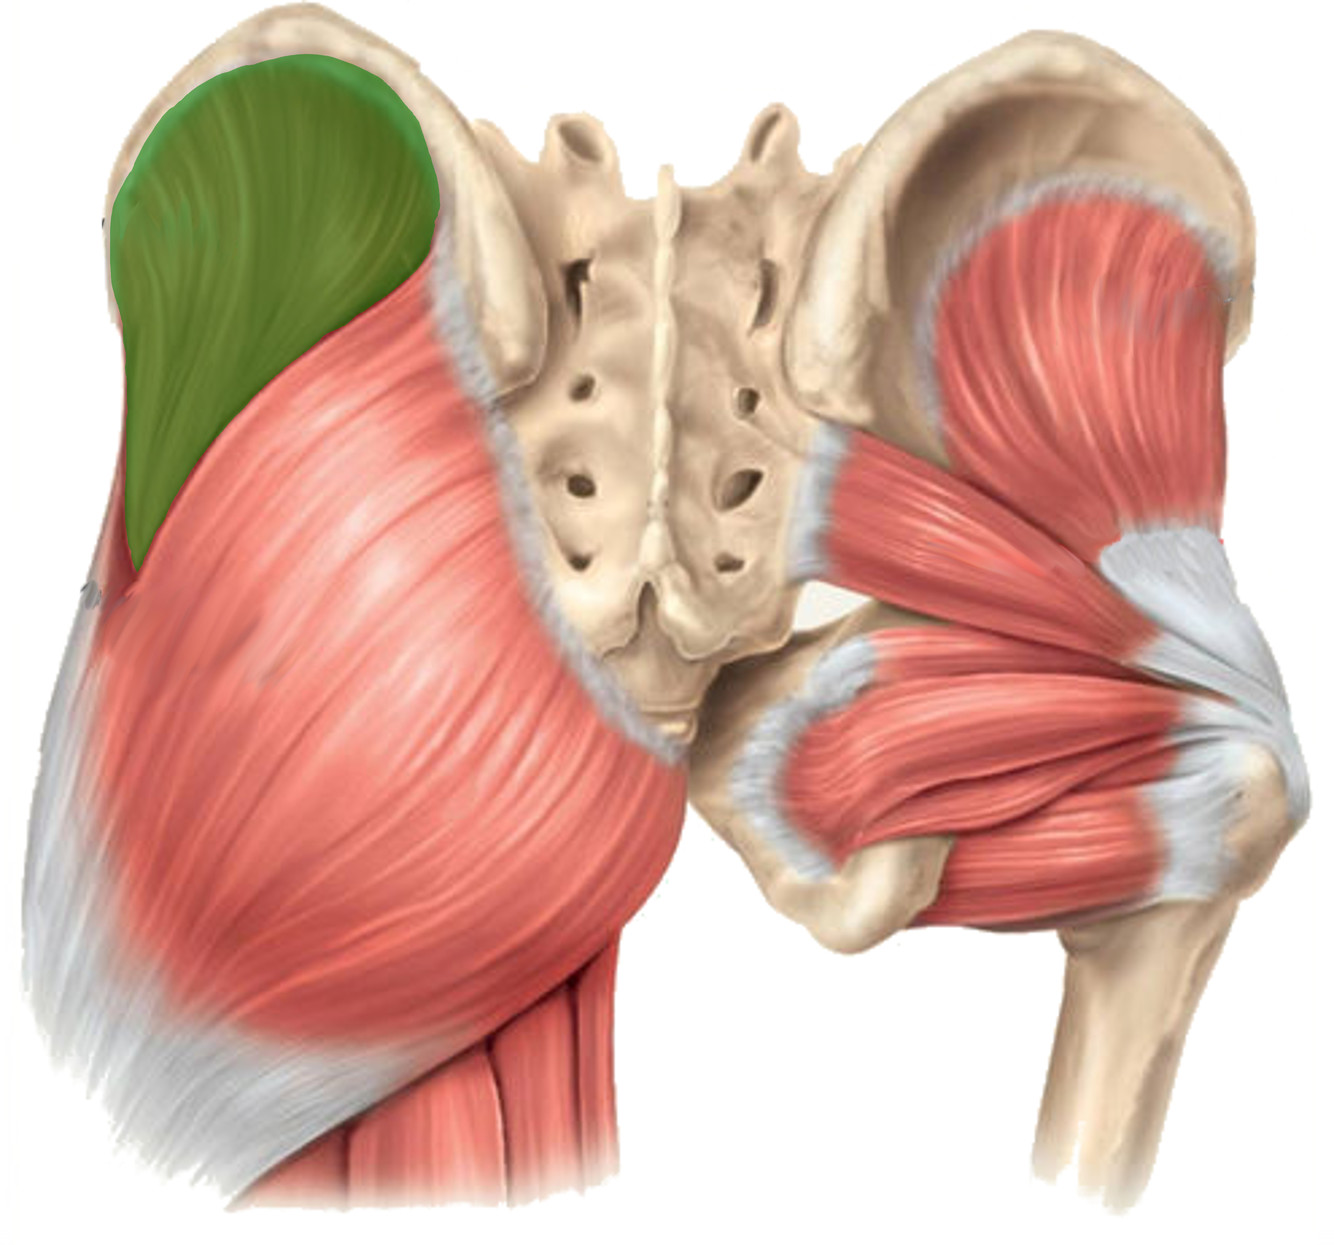

What is the innervation of this muscle (nerve roots)?

Muscle - Obturator internus

L5 + S1

What is the innervation of this muscle?

Muscle - Gluteus medius

Superior gluteal nerve

L4-S1

What is the innervation of this muscle (nerve roots)?

Muscle - Superior gemelli

L5 + S1